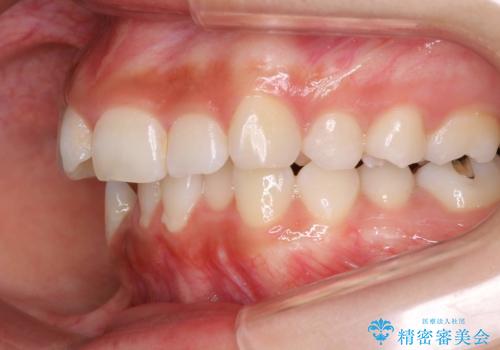

- 前歯のがたつきと出っ歯が気になるとのことで来院されました。

上顎の前から4番目の歯を両側合計2本抜歯して矯正することとなりました。

抜歯をして矯正をすることで、前歯を後方に移動させ、ガタガタを改善することができました。